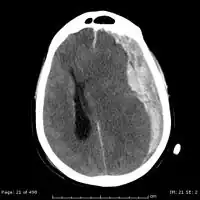

-

Acute-on-chronic subdural hematoma -

Acute traumatic subdural hematoma -

Acute on chronic subdural hematoma -

A subdural hematoma demonstrated by CT

Subdural hematomas occur most often around the tops and sides of the frontal and parietal lobes.[9][10] They also occur in the posterior cranial fossa, and near the falx cerebri and tentorium cerebelli.[9] Unlike epidural hematomas, which cannot expand past the sutures of the skull, subdural hematomas can expand along the inside of the skull, creating a concave shape that follows the curve of the brain, stopping only at dural reflections like the tentorium cerebelli and falx cerebri.

On a CT scan, subdural hematomas are classically crescent-shaped, with a concave surface away from the skull. However, they can have a convex appearance, especially in the early stages of bleeding. This may cause difficulty in distinguishing between subdural and epidural hemorrhages. A more reliable indicator of subdural hemorrhage is its involvement of a larger portion of the cerebral hemisphere. Subdural blood can also be seen as a layering density along the tentorium cerebelli. This can be a chronic, stable process, since the feeding system is low-pressure. In such cases, subtle signs of bleeding—such as effacement of sulci or medial displacement of the junction between gray matter and white matter—may be apparent.

Fresh subdural bleeding is hyperdense, but becomes more hypodense over time due to dissolution of cellular elements. After 3–14 days, the bleeding becomes isodense with brain tissue and may therefore be missed.[22] Subsequently, it will become more hypodense than brain tissue.